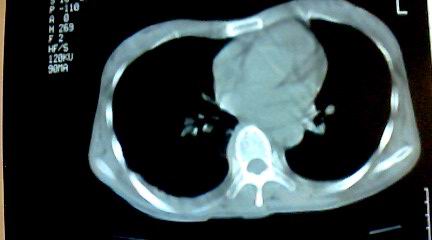

标题: CT25218:请教!胸部CT,胸8椎体骨质破坏,伴周围软组织肿。

患者,女41岁,肢体乏力。

两肺上叶继发性肺结核;胸椎结核并椎旁寒性脓肿形成。

胸椎结核并椎旁寒性脓肿形成。